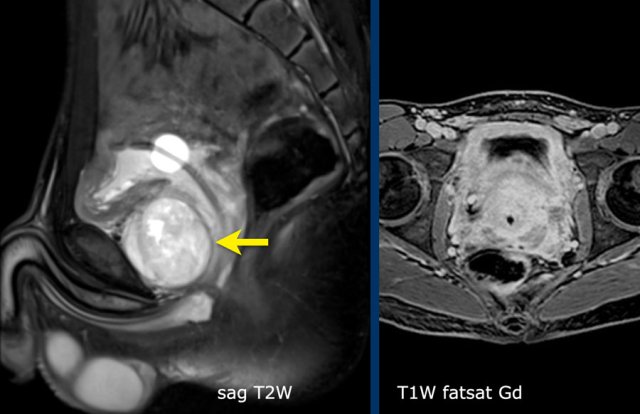

Example 1

A fifteen-year-old boy with a tumor with a small cystic part (arrow) is seen near the bladder.

Balloon of a catheter in the bladder.

MRI

A sagittal image shows a tumor anterior to the bladder neck.

There

is patchy enhancement.

DWI

showed strong diffusion restriction (not shown).

The location of the tumor makes a rhabdomyosarcoma the most likely diagnosis.

The tumor was biopsied through an anterior approach over the pubic bone.

Final diagnosis: Rhabdomyosarcoma